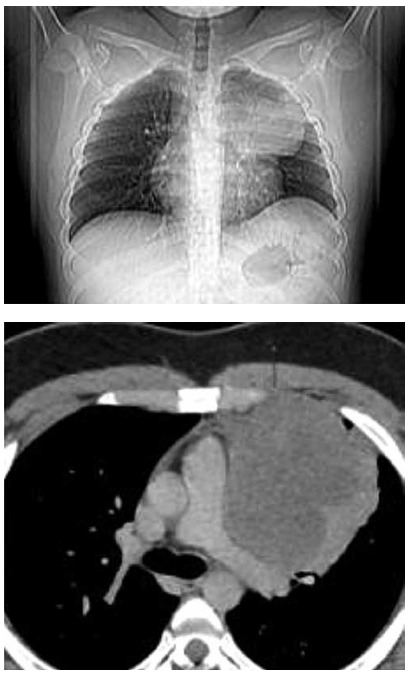

Paciente de 19 anos procura unidade básica de saúde

com queixa de dor em região anterior de hemitórax

esquerdo. Fez radiografia e tomografia, apresentadas a

seguir. Foi submetido a biópsia transtorácica, que revelou

neoplasia maligna com padrão morfológico de pequenas

células redondas e azuis (HE).

(Arquivo pessoal; imagem usada com autorização)

De acordo com o caso clínico e o resultado anatomopatológico, é correto afirmar que se trata de tumor do tipo